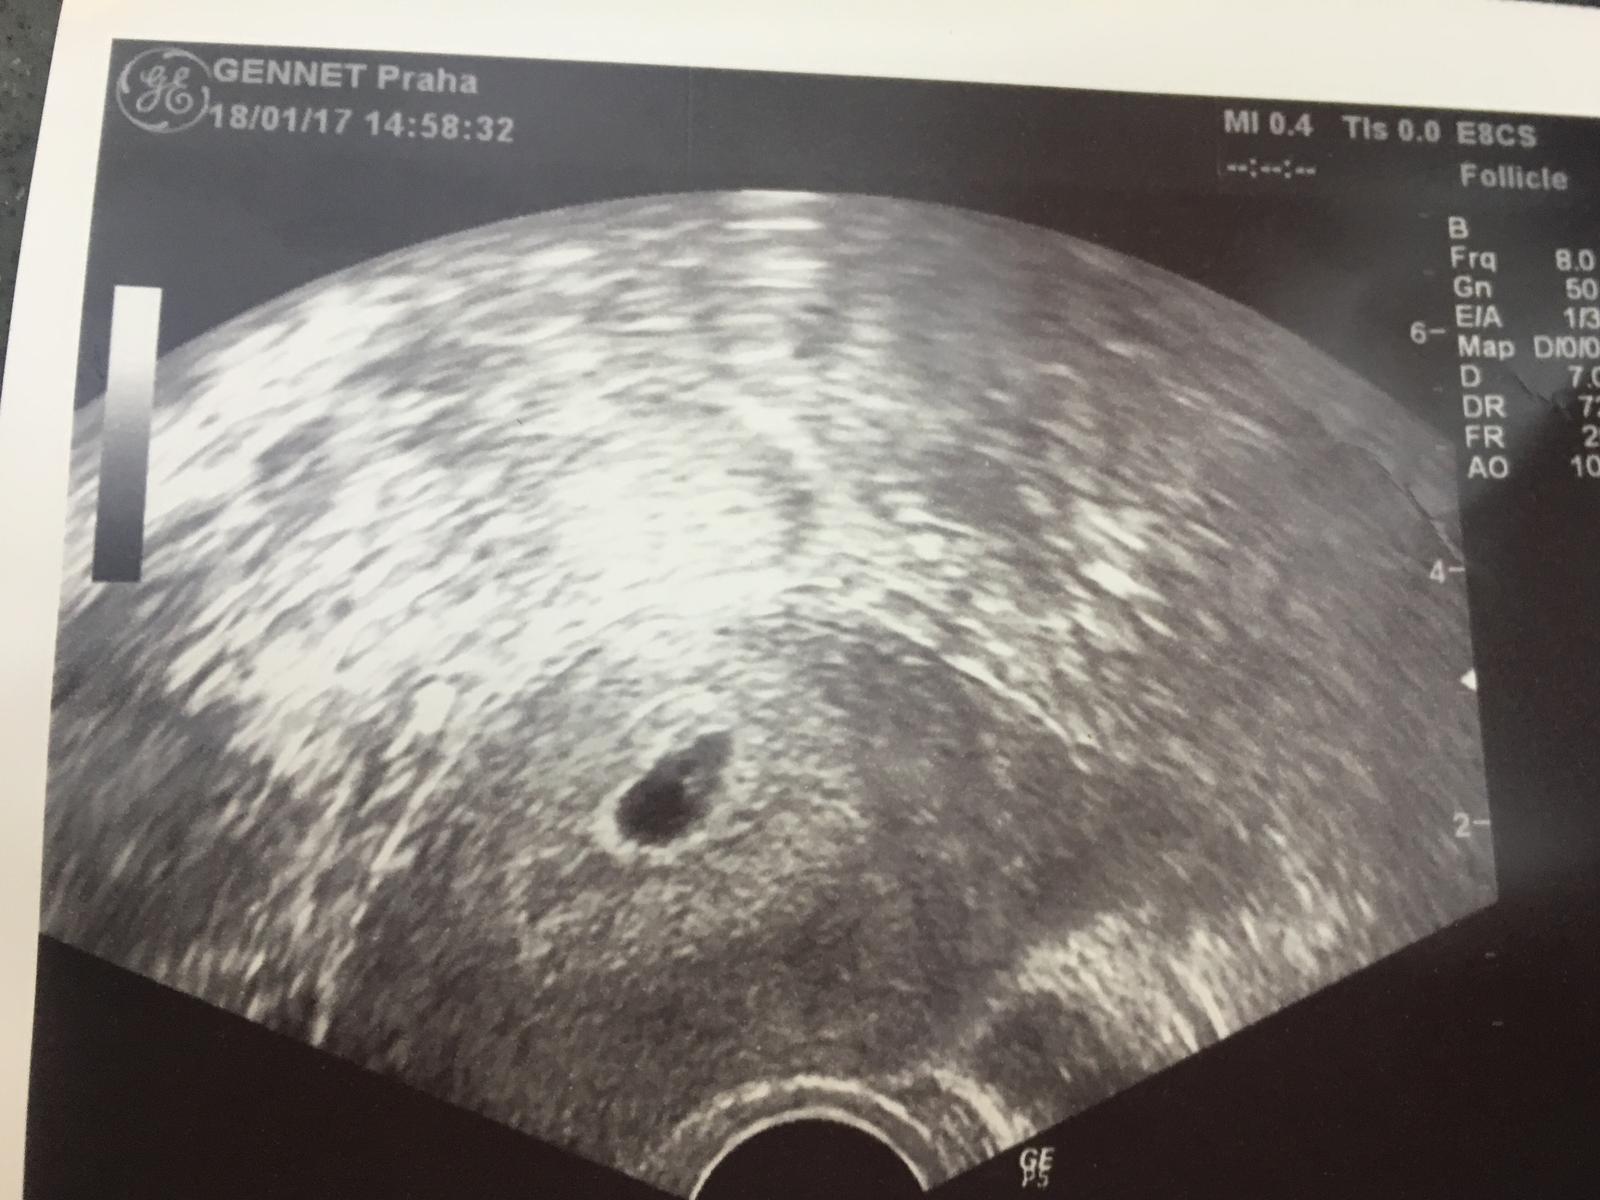

@tornadolu v neděli 22.1.vysazuji prášky budu cekat na MS a pak se hned musim objednat na gindu az po Ms jesi me vyrostla sliznice beru to 3 měsíc tak jsem zvědavá no nějaká smutná jsem znáš to...😢